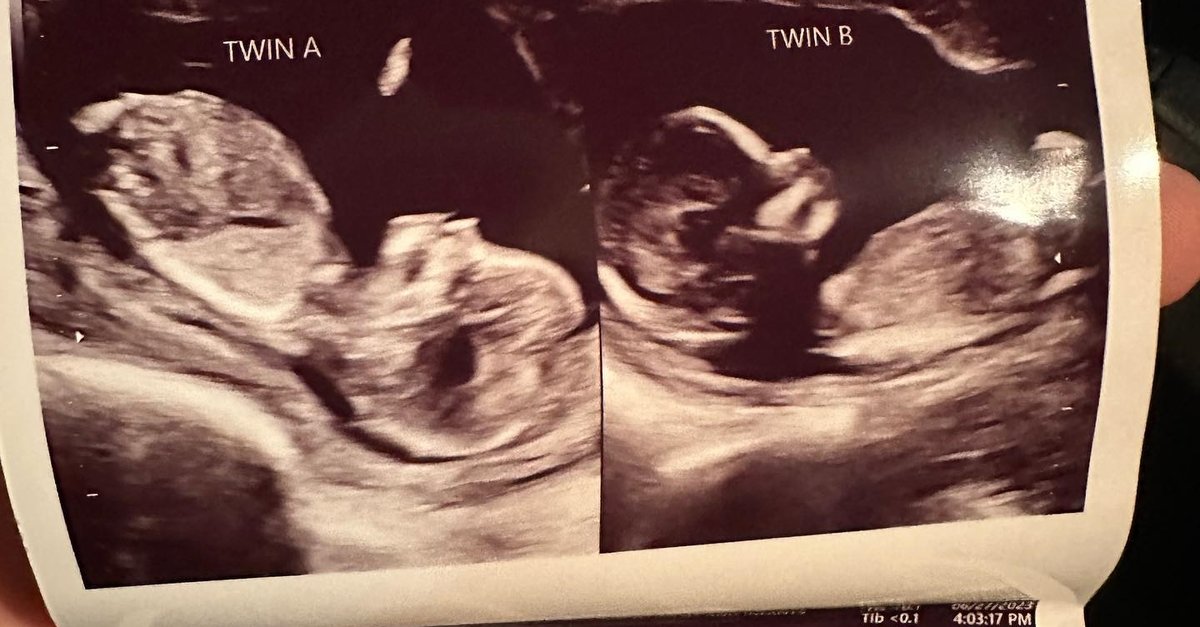

Gerçekleşmesi milyonda bir olan ihtimal olan olay ABD'de gerçekleşti. Doğuştan çift rahmi olan Kelsey Hatcher isimli bir kadın, iki rahminde iki ayrı bebeğe aynı anda hamile kaldı. Hatcher, bebeklerin ikiz mi olacağı konusunda henüz bir bilgi veremediklerini söyledi.

ABD'de yaşayan Kelsey Hatcher isimli bir kadın, doğuştan çift rahmi olduğunu ve nadir görülen bir hamilelikle her iki rahminde de kız bebek beklediğini duyurdu. Hatcher'ın doktoru, genç kadının iki rahminde iki ayrı bebeğe aynı anda hamile kalmasının milyonda bir olduğunu ifade etti.

ABD'nin Alabama eyaletinde yaşayan 32 yaşında, üç çocuk annesi Kelsey Hatcher, uterus didelphys veya iki uterus adı verilen nadir bir uterus anomalisiyle doğdu. Hatcher basına verdiği röportajda, geçen baharda hamile olduğunu öğrenene kadar böyle bir ihtimal olabileceğini bilmediğini ifade etti.

Önceki hamileliklerinde sadece tek bir rahminde bebek taşıyan Hatcher, bebeklerin ikiz mi olacağı konusunda henüz bir bilgi veremediklerini söyledi. Durumunu öğrendikten sonra hamileliğini ve sürecini paylaşmak için özel bir sosyal medya hesabı açan Hatcher, bir bağış kampanyası başlattı.